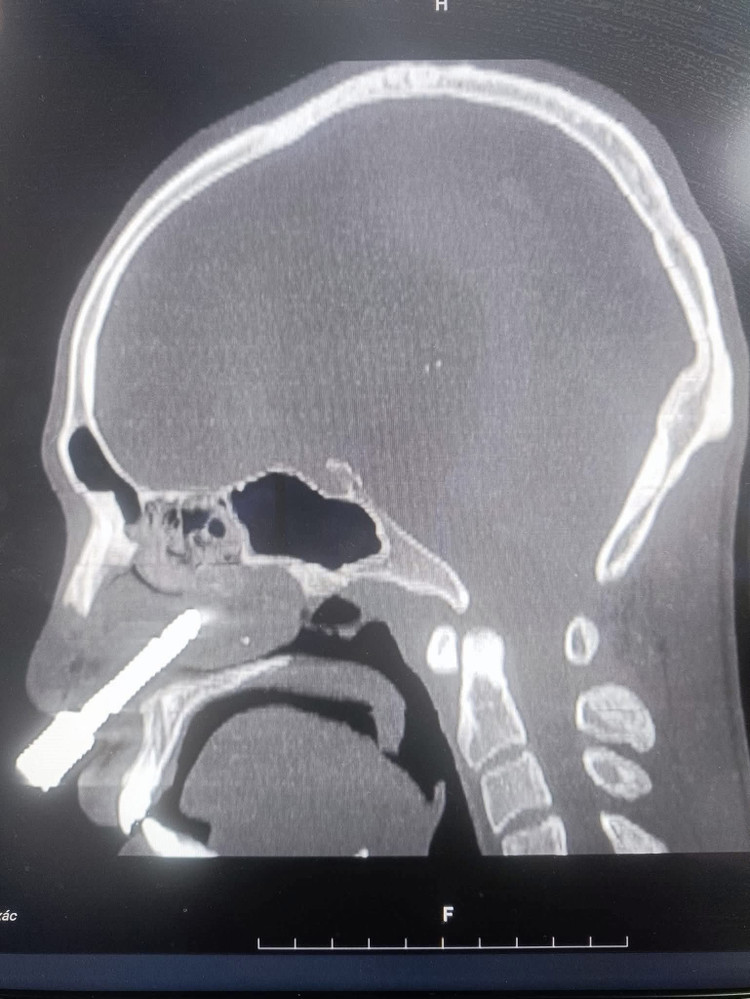

Kết quả chụp cắt lớp vi tính (CT-Scan) và dựng hình ảnh 3D cho thấy dị vật là một mũi khoan kim loại dài khoảng 7–8cm, có hình cong như lưỡi câu.

Kết quả chụp cắt lớp vi tính (CT-Scan) và dựng hình ảnh 3D cho thấy dị vật là một mũi khoan kim loại dài khoảng 7–8cm, có hình cong như lưỡi câu, đâm từ hốc mũi phải xuyên thủng hoàn toàn vách ngăn mũi, đầu móc cong cắm sâu vào hốc mũi trái. Khiến phần cuống mũi dưới bị rách nặng, toàn bộ vách ngăn bị thủng lớn. Bệnh nhân được chỉ định phẫu thuật cấp cứu ngay lập tức.